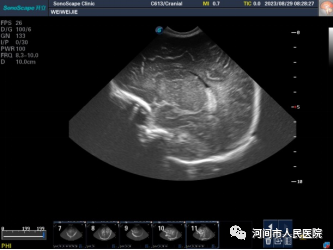

▲新生儿脑室内出血